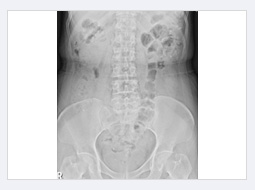

대장통과시간검사